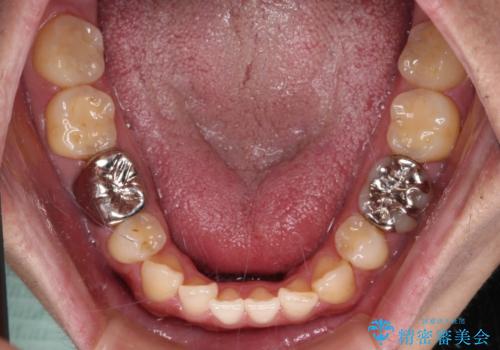

- 抜歯矯正の後戻りを気にして来院された患者様です。

舌の突出癖によるオープンバイトになり、前歯の叢生が後戻りしていました。

舌のトレーニングを行いながら、インビザラインを用いて矯正治療を行うこととしました。

インビザラインの特性を活用して奥歯の咬み合わせを圧下させることで、前歯のオープンバイトを改善さえることができました。